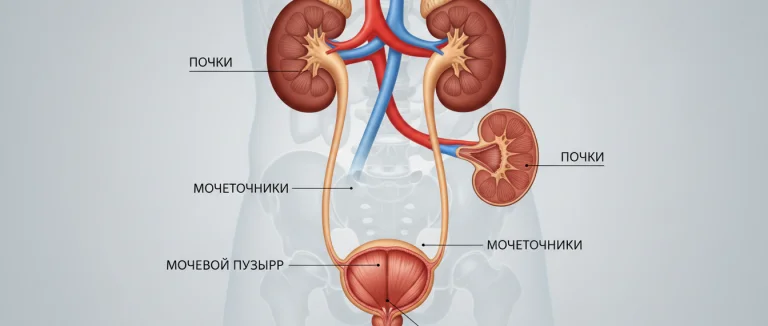

повторные УИ

почечные камни

признаки ИМП

продукты при УТИ

простатическая уретра